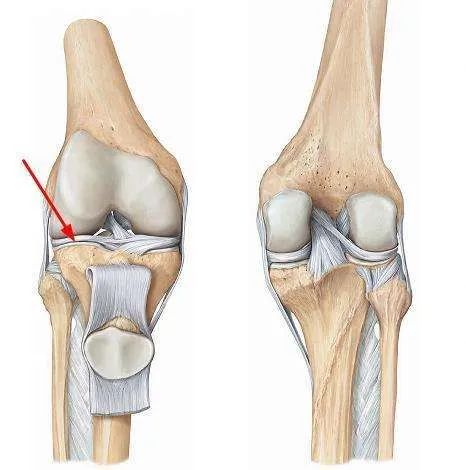

关节的寿命是有限的。一旦关节“气数已尽”,就会引发各种关节病! 关节的寿命主要是由基因决定的,一般的健康寿命是 60 年,过度使用会加重对它的磨损,并且不可修复。

还有一个更扎心的事实是女性的膝关节天生不完美,一项对中国膝关节骨关节炎的患病率及危险因素进行的大样本调查发现,我国膝关节炎发病率女性为 10.3%,男性为 5.7%,女性明显高于男性。

我国约有 1.2 亿人患有骨关节炎:

50 岁以上,约 50% 被膝骨关节炎困扰

60 岁后患病率达 60%

70 岁以上,几乎每个老年人都会患此病

无论男女都应该保养膝盖,尤其是 30 岁以后。